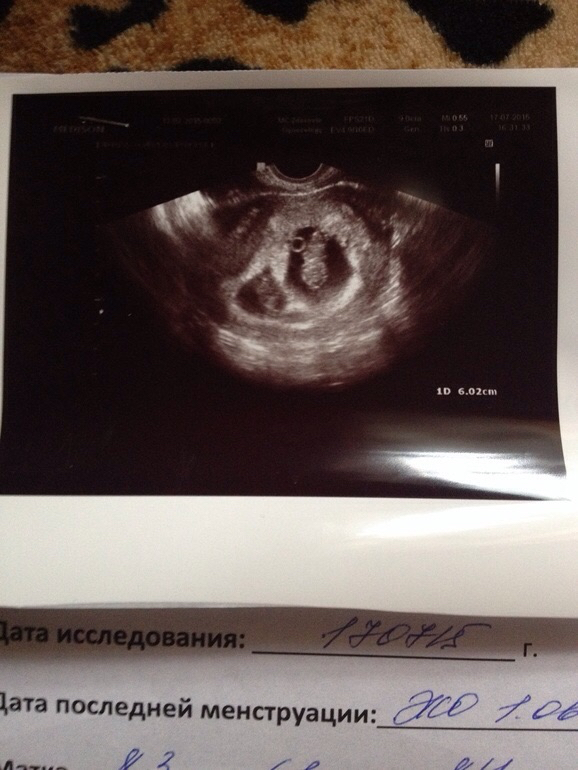

Девочки посмотрите узи пожалуйста

Может быть. До этого делала 2 раза узи разница была 1-2 мм. А тут вот столько

не получилось скрыть Б Узи